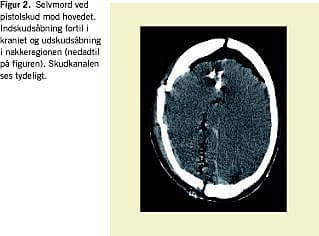

I skudsager (Figur 2) kan CT anvendes til at lokalisere projektiler og fragmenter og som hjælp til bestemmelse af skudretningen [13-17]. Ved haglskudlæsioner kan haglfordelingen vurderes. Ved terrorbombeangreb kan der hurtigt opnås et overblik over sprængfragmenter [18].